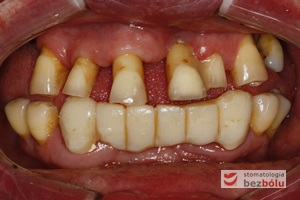

Pozytywna przemiana uśmiechu - odbudowa protetyczna na implantach - obraz kliniczny przed terapią stomatologiczną

Pozytywna przemiana uśmiechu – obraz kliniczny przed terapią stomatologiczną

Stan wyjściowy - patologiczne wychylenie zębów górnych, liczne braki zębowe w szczęce i żuchwie, nieproporcjonalnie małe zęby do podstaw kostnych

Stan wyjściowy – patologiczne wychylenie zębów górnych, liczne braki zębowe w szczęce i żuchwie, nieproporcjonalnie małe zęby do podstaw kostnych

Braki zębowe w strefach bocznych szczęki i żuchwy - widoczne starcie patologiczne na skutek przeciążeń okluzyjnych w odcinku przednim

Braki zębowe w strefach bocznych szczęki i żuchwy – widoczne starcie patologiczne na skutek przeciążeń okluzyjnych w odcinku przednim